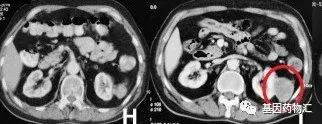

至20个月后的2013年2月,患者出现了黄疸和瘙痒,肝功能检查异常,腹部增强CT检查提示,小细胞肺癌发生了胰头部转移,胆总管也发生了梗阻。

经过支架置入术等外科治疗后,患者的梗阻性胆管症状有所缓解,于是又一次地接受了伊立替康+卡铂方案化疗,同样是6个周期。影像学检查结果提示,部分缓解。